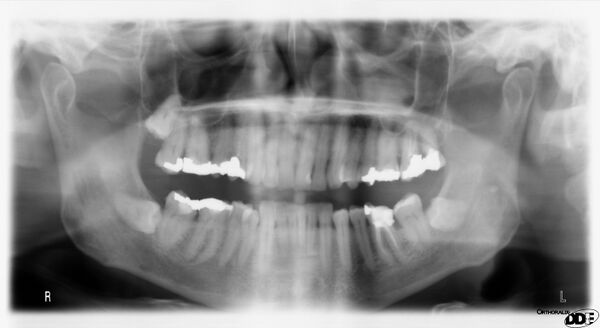

Ортопантомография (от греч.: orthos — прямой, правильный, pan — всё, tomos — ломоть, отрезанный кусок и grapho — писать, рисовать) — особый вид рентгеновской съёмки костей лицевого скелета, при котором они «развёртываются» в одну плоскость[1]. Другими словами рентгенологическое исследование в стоматологии, челюстно-лицевой хирургии, косметологии, позволяющее получать развёрнутое изображение всех зубов с челюстями, прилежащими отделами лицевого скелета. Является первичным рентгенологическим исследованием[2].

5. Контроль этапов лечения и динамики течения заболеваний (качество пломбировки канала, штифты, имплантаты и пр.).

Галерея